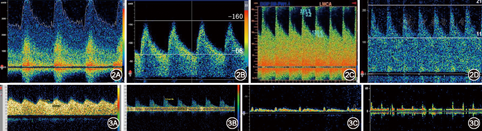

(1)动脉狭窄(图2A):表现为动脉流速增快,伴涡流、湍流,声频粗糙以及节段性血流改变[8];(2)代偿增快(图2B):表现为动脉流速增快,但频谱形态正常,出现于邻近动脉有狭窄或闭塞时,例如颈内动脉严重狭窄或闭塞后,如果前交通动脉开放,对侧大脑前动脉血流速度会代偿性增快[8];(3)动静脉畸形的供血动脉(图2C):表现为动脉流速增快,伴搏动指数减低及隆隆样杂音[8];(4)血管痉挛(图2D):表现为均匀一致、一条或者多条动脉出现流速增快。在临床上,由TCD直接诊断的血管痉挛非常少见。常见于蛛网膜下腔出血、颅脑外伤和可逆性血管收缩综合征等[8]。

(1)狭窄远段(图3A):重度狭窄或者闭塞部位远段的动脉内压力减低,血流速度减慢,远端阻力小动脉代偿性扩张,导致搏动指数减低,TCD表现为低流速低搏动指数的"波浪状"频谱[8]; (2)狭窄近段(图3B):由于动脉狭窄前阻力增高,舒张期血流下降更显著,TCD出现血流速度减慢、搏动指数增高的频谱[8];(3)锁骨下动脉盗血:盗血侧VA可以表现为血流速度减慢(图3C)——常伴有收缩期切迹,或者收缩期血流方向逆转等变化;需注意,VA开口重度狭窄或闭塞时,VA也可以表现为类似的切迹改变[8]。(4)脑死亡(图3D):表现为动脉血流速度减慢,搏动指数异常增高,舒张期血流方向逆转或者血流消失。